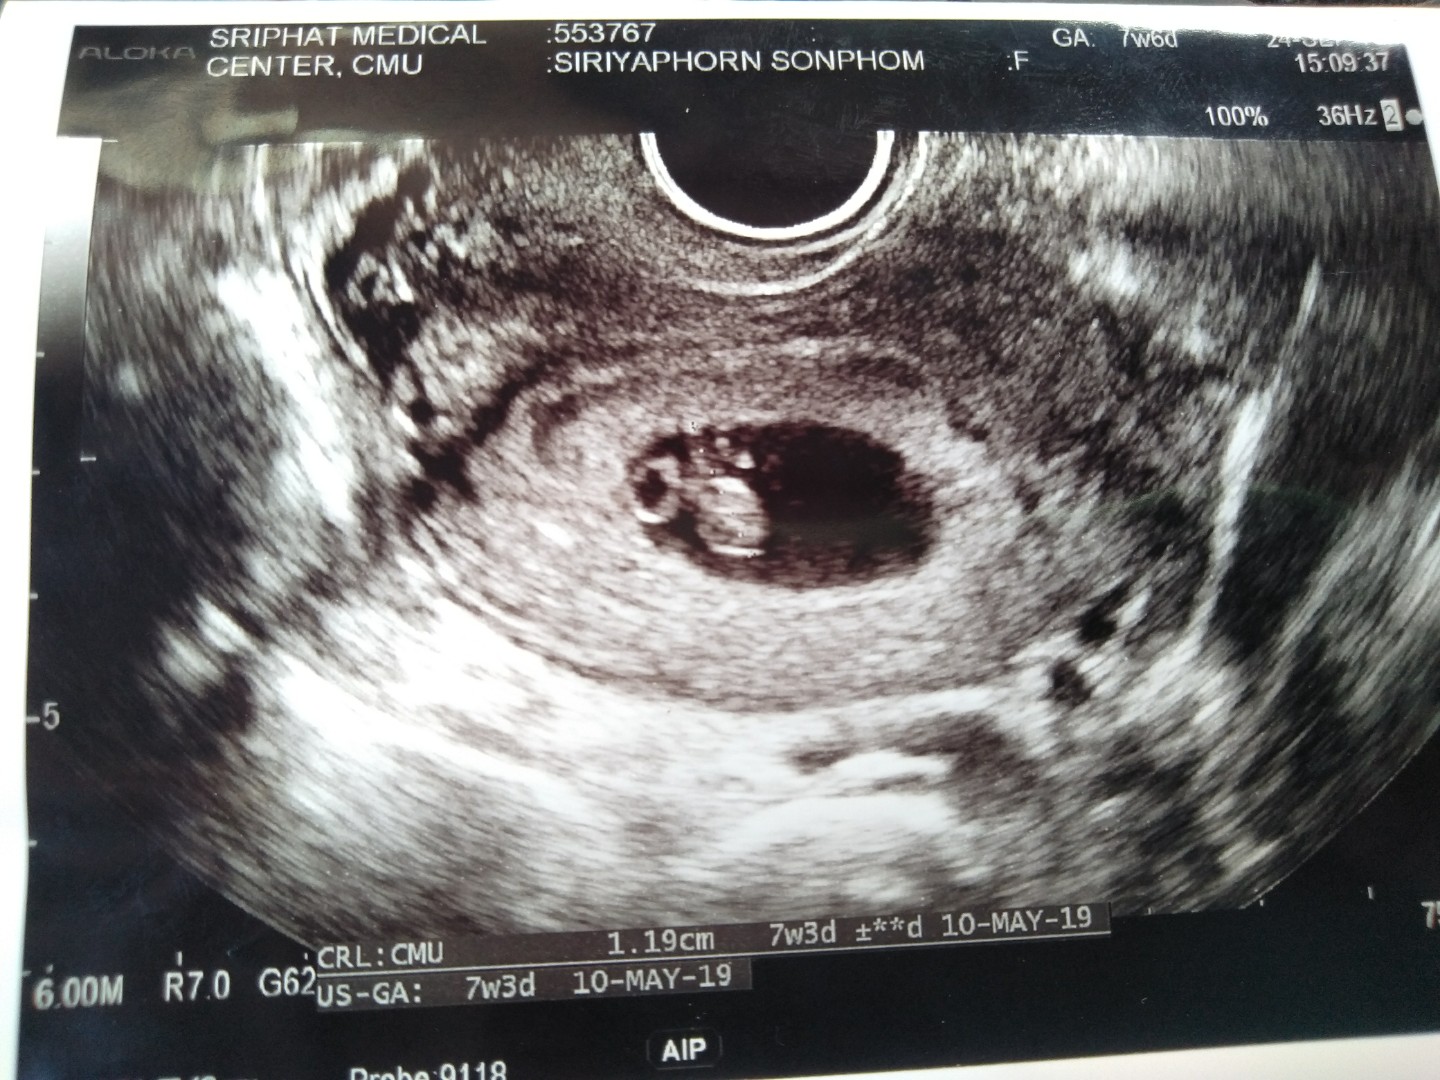

มาอวดภาพแรกของเจ้าตัวน้อยกันคะ

อยากเห็นภาพแรกของเจ้าตัวน้อย. ของแม่ๆ. แต่ละบ้านบ้างอะคะ. มาแชร์ประสบการณ์กันได้นะคะ❤️

29wจ้า